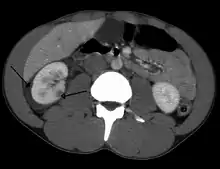

| Abdominal trauma resulting in a right kidney contusion (open arrow) and blood surrounding the kidney (closed arrow) as seen on CT | |